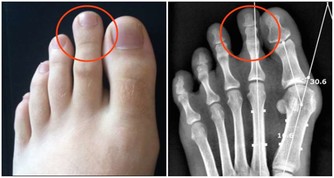

空鼻症到底是什麼?即過分的鼻甲切除性手術導致的鼻腔黏膜萎縮及一系列伴發症狀。

“患者一般是之前患有慢性鼻炎、鼻息肉、鼻竇炎等鼻部病症,想通過手術通暢鼻腔,

但手術後感覺還是不夠通暢或者過度通暢,部分患者就成了空鼻症。”